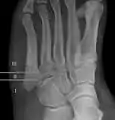

לסיבות שונות, שבר ג'ונס עלול לא להתאחה מכיוון שהדיאפיזה (גוף העצם), האזור שבו מתרחש השבר (אזור II), הוא אזור שאספקת הדם בו מעוטה. בנוסף, ישנם גידים שונים, כמו השריר השוקיתי הקצר, השריר השוקיתי השלישי ושני השרירים המחוברים לעצם שעלולים למשוך את שני צדדי השבר ולמנוע אותו מלהתאחה.

החיבור בין האזורים I ו-III הוא אמנם יחסית חזק, אך הוא מגביל את התנועה בצורה מעוטה. מצד שני, אזור II השני אינו מחובר באופן חזק, וכתוצאה מכך, ישנה הסכמה כללית ששברים באזור זה נחשבים כסוג של אימוביליזציה פנימית.

הבחנה בין אזורים אלה הוא דבר חשוב מבחינה קלינית, וניתן לעשות אותו באופן אנטומי וגם באמצעות קרני רנטגן.[9] לעיתים התערבות כירורגית כרוכה בסיבוכים, ולא תמיד מובילה להחלמת והתאחות השבר. דעות שמרניות, מעדיפות טיפול ללא ניתוח בשברי ג'ונס אצל אנשים שאינם ספורטאים.[10]

- שלושה אזורים מתוארים

- שני אזורים מתוארים